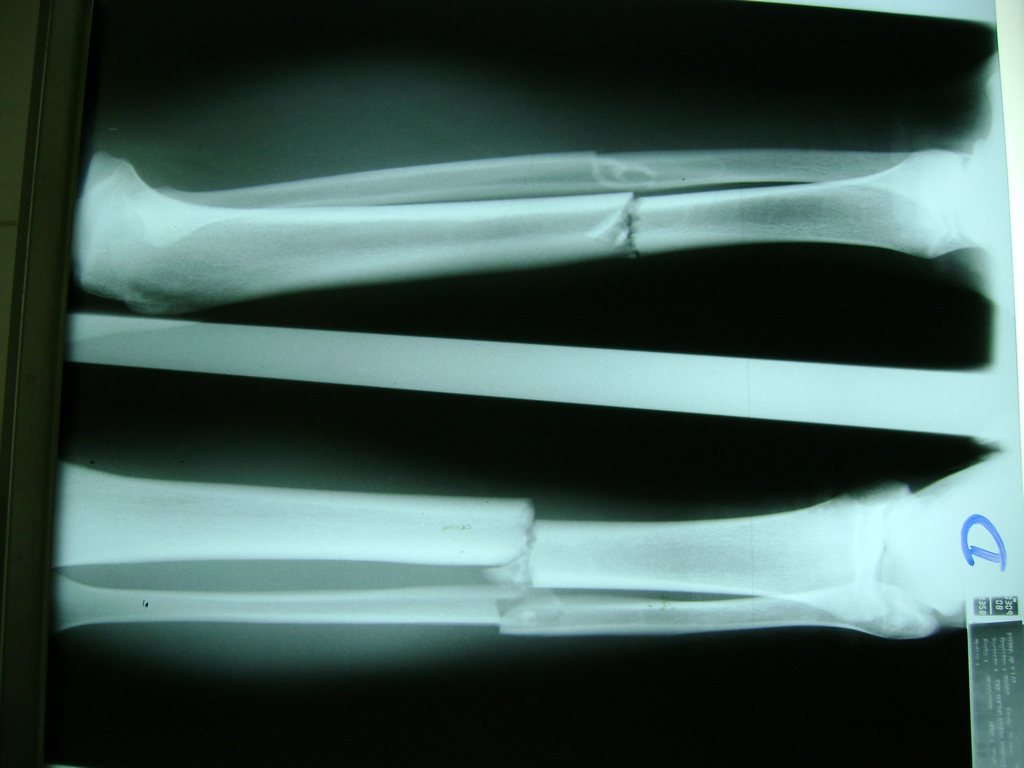

Cirugías de Hombros - Perone y Tibia

Aunque cada uno de estos huesos puede fracturarse por separado, normalmente la rotura es una lesión que se produce de forma conjunta

La mayor parte de las roturas implican a la parte proximal del hueso (parte del hueso próximo a la rodilla) o a la parte distal (parte del hueso cerca del tobillo).

Debido a la fina cobertura de piel que recubre la tibia y el peroné, las fracturas generalmente son abiertas, es decir, el hueso roto rasga la piel, atravesándola. Las fracturas de tibia y peroné generalmente se producen por un fuerte impacto o torsión.